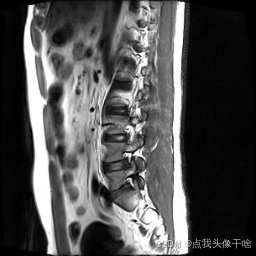

想象一下,你给AI看一张脊椎的核磁共振(MRI)照片,它就能像经验丰富的医生一样,把照片里每一块骨头、每一节椎间盘都给你清清楚楚地标记出来。这个系统干的就是这个酷炫的事儿!

- 原图:就是一张张脊椎的MRI扫描图。